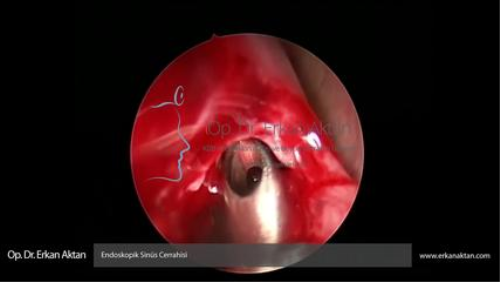

Endoskopik Sinüs Cerrahisi - Op. Dr. Erkan Aktan

Op. Dr. Erkan Aktan “Endoskopik sinüs cerrahisi” işlemini gerçekleştiriyor.